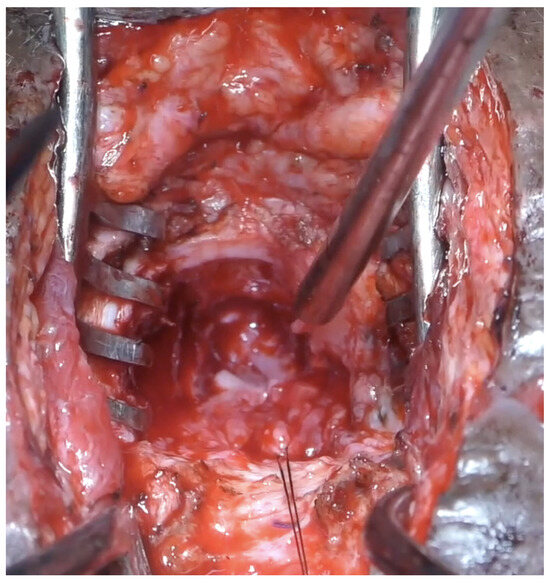

Figure 4.

Clinical picture of a girl after surgical revision of a pelvic fracture urethral injury.

Surgical repair was performed through a lower abdominal incision. The extraperitoneal space was entered and the bladder was released from its anterior attachments. A posterior and superior pubectomy was then performed (Figure 5). Scar tissue at the site of injury was excised. The urethra distal to the injury was incised over a dilator passed through the urethra from the meatus (Figure 6).

A 12 Fr mini nephroscope was passed through the suprapubic catheter site to guide the incision of the bladder. The anastomosis between the bladder neck and the urethra was performed with six 5-0 polydiaxone sutures. The posterior sutures were tied down (Figure 7) before passing a 14Fr silicon catheter across the anastomosis and tying down the anterior sutures. The omentum was mobilized and transposed onto the anastomosis. A drain was not usually required.

Figure 7.

Anastomosis.